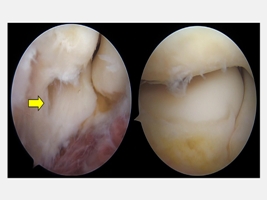

陳重宇醫師說,外側手肘疼痛並非全是「網球肘」,其他常見原因包括:韌帶或關節囊損傷、剝離性軟骨炎、骨刺或退化性關節炎、滑膜皺襞症候群(synovial plica syndrome)和神經壓迫性疼痛。針對手肘的結構性病因,微創關節鏡手術是一個安全且效果良好的選擇。以C小姐為例,手術透過關節鏡直接觀察肘關節內部結構,精準鬆解發炎的肌腱附著點,並清除增生的滑膜皺襞。手術僅需數個約1公分的小切口,創傷小、出血少,術後疼痛明顯減輕,復原速度快。